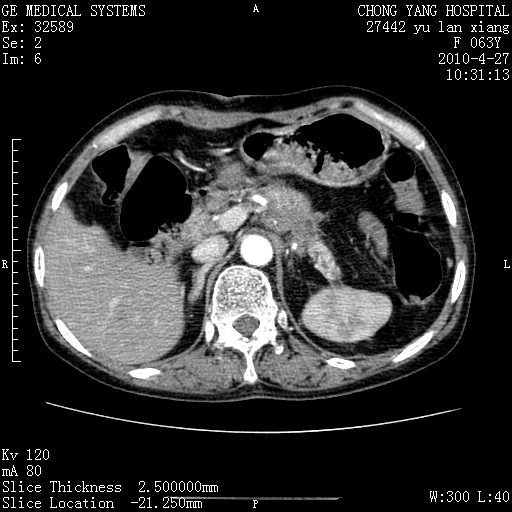

标题: CT26066:F63Y 上腹正中压痛半月,CA199:7400u/ml,MR示胰腺炎伴 [打印本页]

胰腺癌侵犯腹腔动脉干-分支、胃壁、左侧膈肌伴胰周及腹膜后淋巴结转移、胆囊切除术后。

胰腺癌侵犯腹腔动脉干-分支、胃壁、左侧膈肌伴胰周及腹膜后淋巴结转移、胆囊未显影。